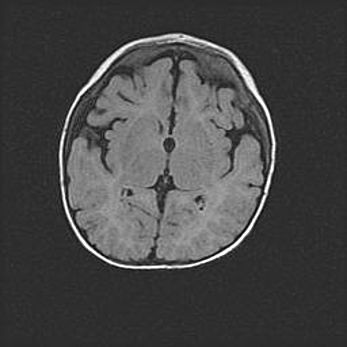

Сообщающаяся гидроцефалия. Кистозная энцефаломаляция головного мозга.

Возраст: 3 месяца 4 дня

Вес: 3100 г

Пол: женский

Окружность головы: 34 см

Срок гестации: 31 неделя

Кистозная энцефаломаляция головного мозга - одна из форм поражения головного мозга в детском возрасте. Характеризуется возникновением множественных и распространённых кист в коре, белом веществе и подкорковых образованиях головного мозга у плодов, новорождённых и детей раннего возраста. Развитие кистозной энцефаломаляции связано с внутриутробной асфиксией и гипотонией, родовой травмой, тромбозом синусов, пороками развития сосудов, инфекциями, сепсисом и другими причинами. Наиболее значимые инфекционные агенты: вирусы простого герпеса, цитомегалии, краснухи, токсоплазмы, энтеробактерии, золотистый стафилококк и другие.